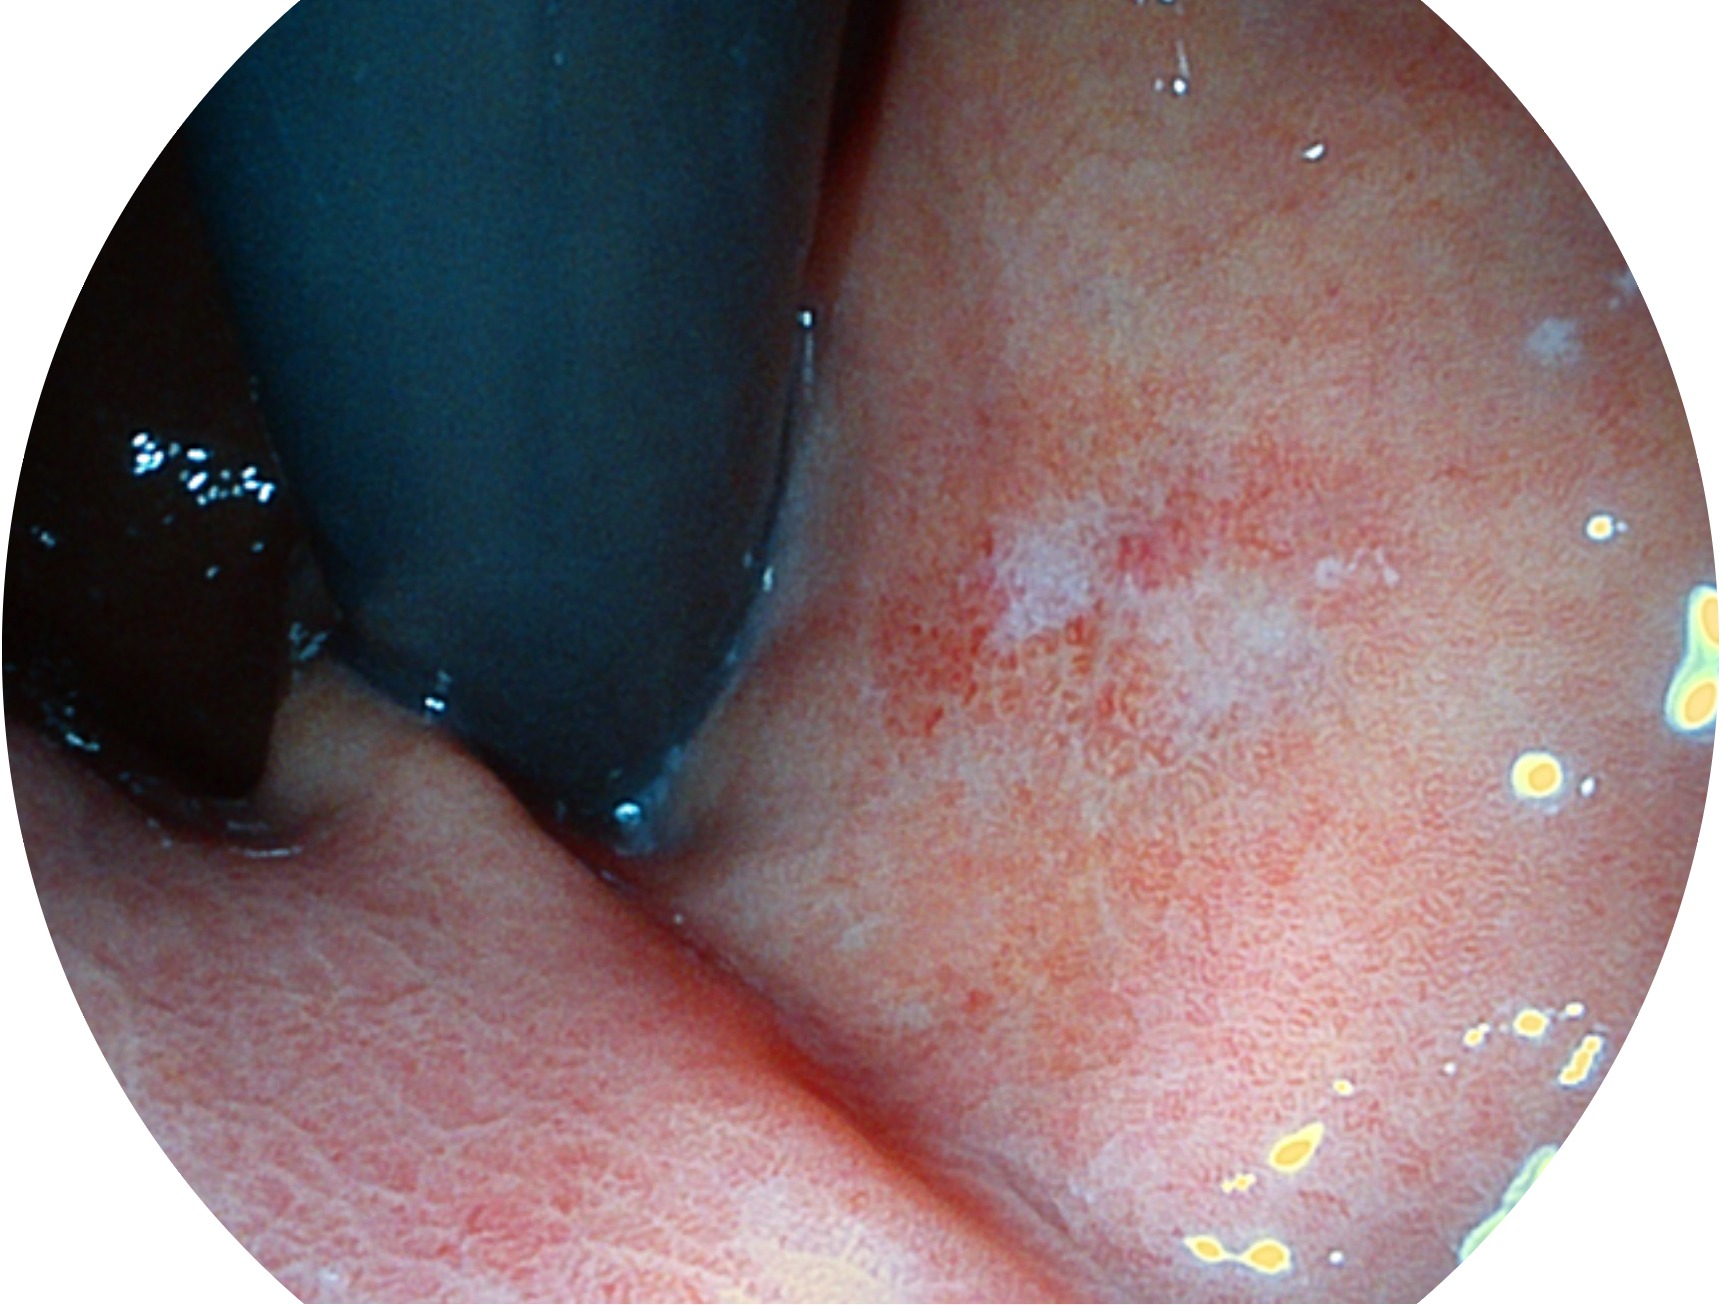

開立新開發(fā)的內(nèi)鏡染色技術(shù),主要是基于多波長LED 光源的開發(fā),VLS-55Q 四波長LED 光源是由四個(gè)不同顏色的LED光按照相應(yīng)照明模式所規(guī)定的特定發(fā)光比例進(jìn)行合束后形成,合束后形成的照明光的光譜由紅光、綠光、藍(lán)光及藍(lán)紫光這四個(gè)不同的波段范圍構(gòu)成。具有更高光譜自由度,通過光譜比例的控制,實(shí)現(xiàn)了聚譜成像技術(shù),英文全稱為“Spectral Focused Imaging, SFI”,縮寫為“SFI”和光電復(fù)合染色成像技術(shù),英文全稱為“Versatile Intelligent Staining Technology, VIST”,縮寫為“VIST”。